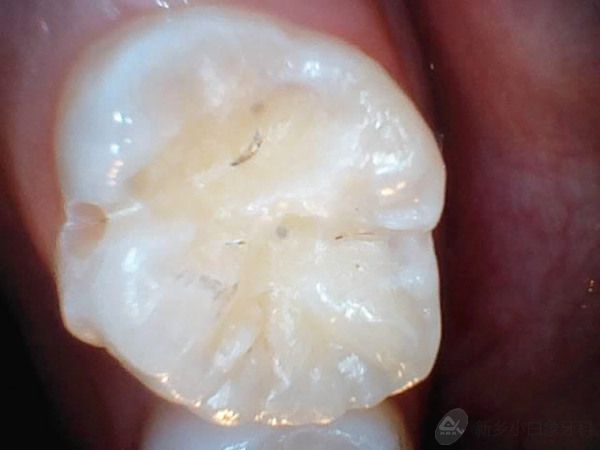

患者廉某某,女,10岁,患儿家长发现患儿牙齿有洞,影响进食,于2014年12月11日来诊。

检查:16合面及颊沟龋坏达牙本质浅层,探诊(-),叩诊(-),温度测试正常,牙龈无红肿。

诊断:16中龋

治疗计划:16护充

治疗过程:3%双氧水含漱一分钟,16去腐质,备洞,隔湿干燥,流动纳米充填及行纳米封闭术。